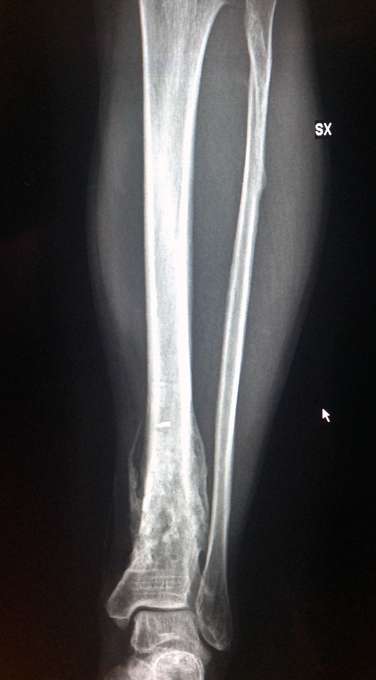

Fatte RX pre-operatorie alla gambaccia: dicono tutto bene....

Ciao in Bocca al Lupo......ma avevi Rotto la Tibia E Il Perone Intatto.....non dovrebbe essere Stata una Grandissima Botta...di Solito Il Perone Si rompe Per Un Non Nulla....

Il perone si era rotto in alto.... Si vede bene.

E alla faccia della NON grandissima botta!!! La tibia si è rotta in 5 pezzi ed avevo il piede girato per più di 45 gradi.